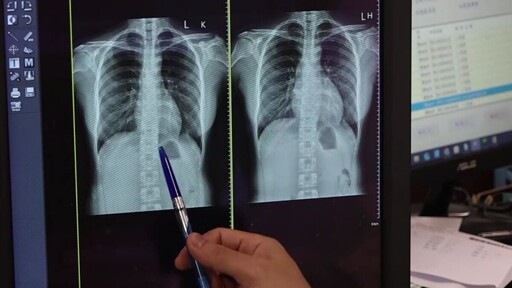

【創新聞 記者張溎壕/彰化報導】心臟衰竭也能逆轉!26歲李姓女子去年例行健檢時,X光片意外顯示心臟比正常大。就醫後發現左心室射出分率僅39%,已符合心臟衰竭定義。經10個月規律服藥與標準治療,心臟功能恢復正常,左心室射出分率提升至59%,接近健康標準。

▲26歲女子例行健檢發現心臟比常人大,左心室射出分率僅39%,接受員榮醫院心臟內科陳裕峰醫師經10個月規律藥物及標準治療後,心臟功能恢復正常。(員榮醫院提供)

這名年輕女子去年健檢時,透過X光片發現心臟比一般人稍大,便前往員榮醫院心臟內科就診,心臟內科陳裕峰醫師今(15)日表示,檢查結果顯示她左心室射出分率只有39%,正常應該至少50%以上,甚至60%以上才算理想,且心臟瓣膜出現較嚴重逆流,符合心臟衰竭標準。

▲26歲女子例行健檢發現心臟比常人大,左心室射出分率僅39%,接受員榮醫院心臟內科陳裕峰醫師經10個月規律藥物及標準治療後,心臟功能恢復正常。(員榮醫院提供)

在陳裕峰醫師的指導下,患者開始規律服藥,並接受心臟衰竭標準治療。經過10個月治療,心臟大小已恢復正常,左心室射出分率也從39%大幅提升至59%,接近正常值。陳醫師指出,心臟衰竭患者除了服藥,也可透過EECP(增強型體外反搏治療)改善心臟功能。